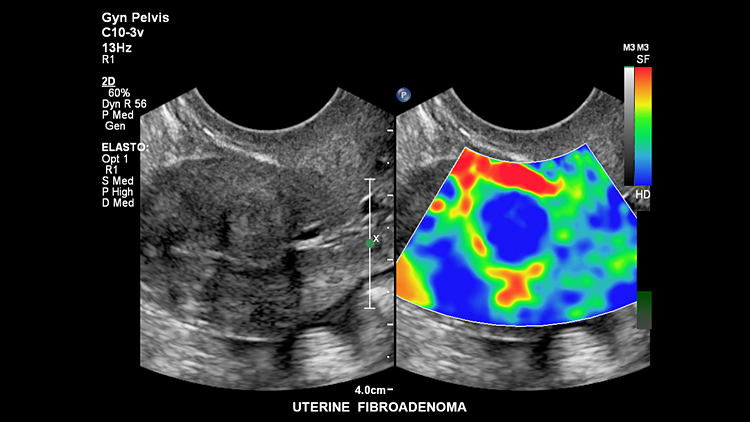

УЗИ аппарат Philips Epiq 7 поддерживает два вида эластографии (компрессионная, со сдвиговой волной). Эти виды визуализации предоставляют достоверные и эффективные результаты исследования жёсткости ткани. Благодаря функции DICOM одновременно просматриваются результаты КТ, МРТ, ангиограммы и прочие ультразвуковые снимки. Технические характеристики оборудования помогают врачу принимать точное и верное решение в процессе интервенционных процедур.

Эластография сдвиговой волной

Соноэластография

Высокочувствительная визуализация на базе анализа деформации не требует внешней компрессии и позволяет оценивать относительную упругос

Фиброаденома матки, C10-3v

Фиброаденома матки, C10-3v